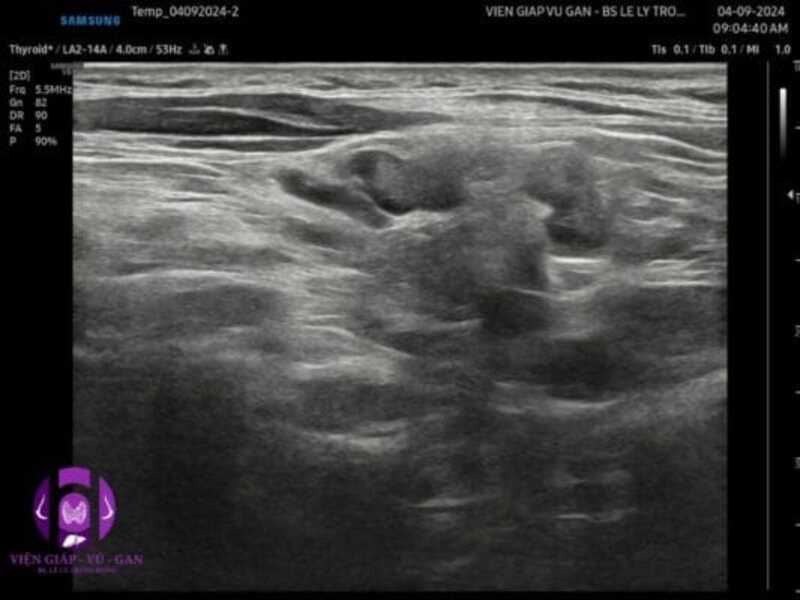

SIÊU ÂM (Samsung V8):

- Vùng trên đòn trái có vài hạch echo kém, còn rốn, nhu mô hạch dày không đều, không vôi, tăng âm phía sau nhẹ, kích thước 8-19mm. Siêu âm doppler ghi nhận mạch máu tăng sinh nhiều và phân bố hỗn độn.